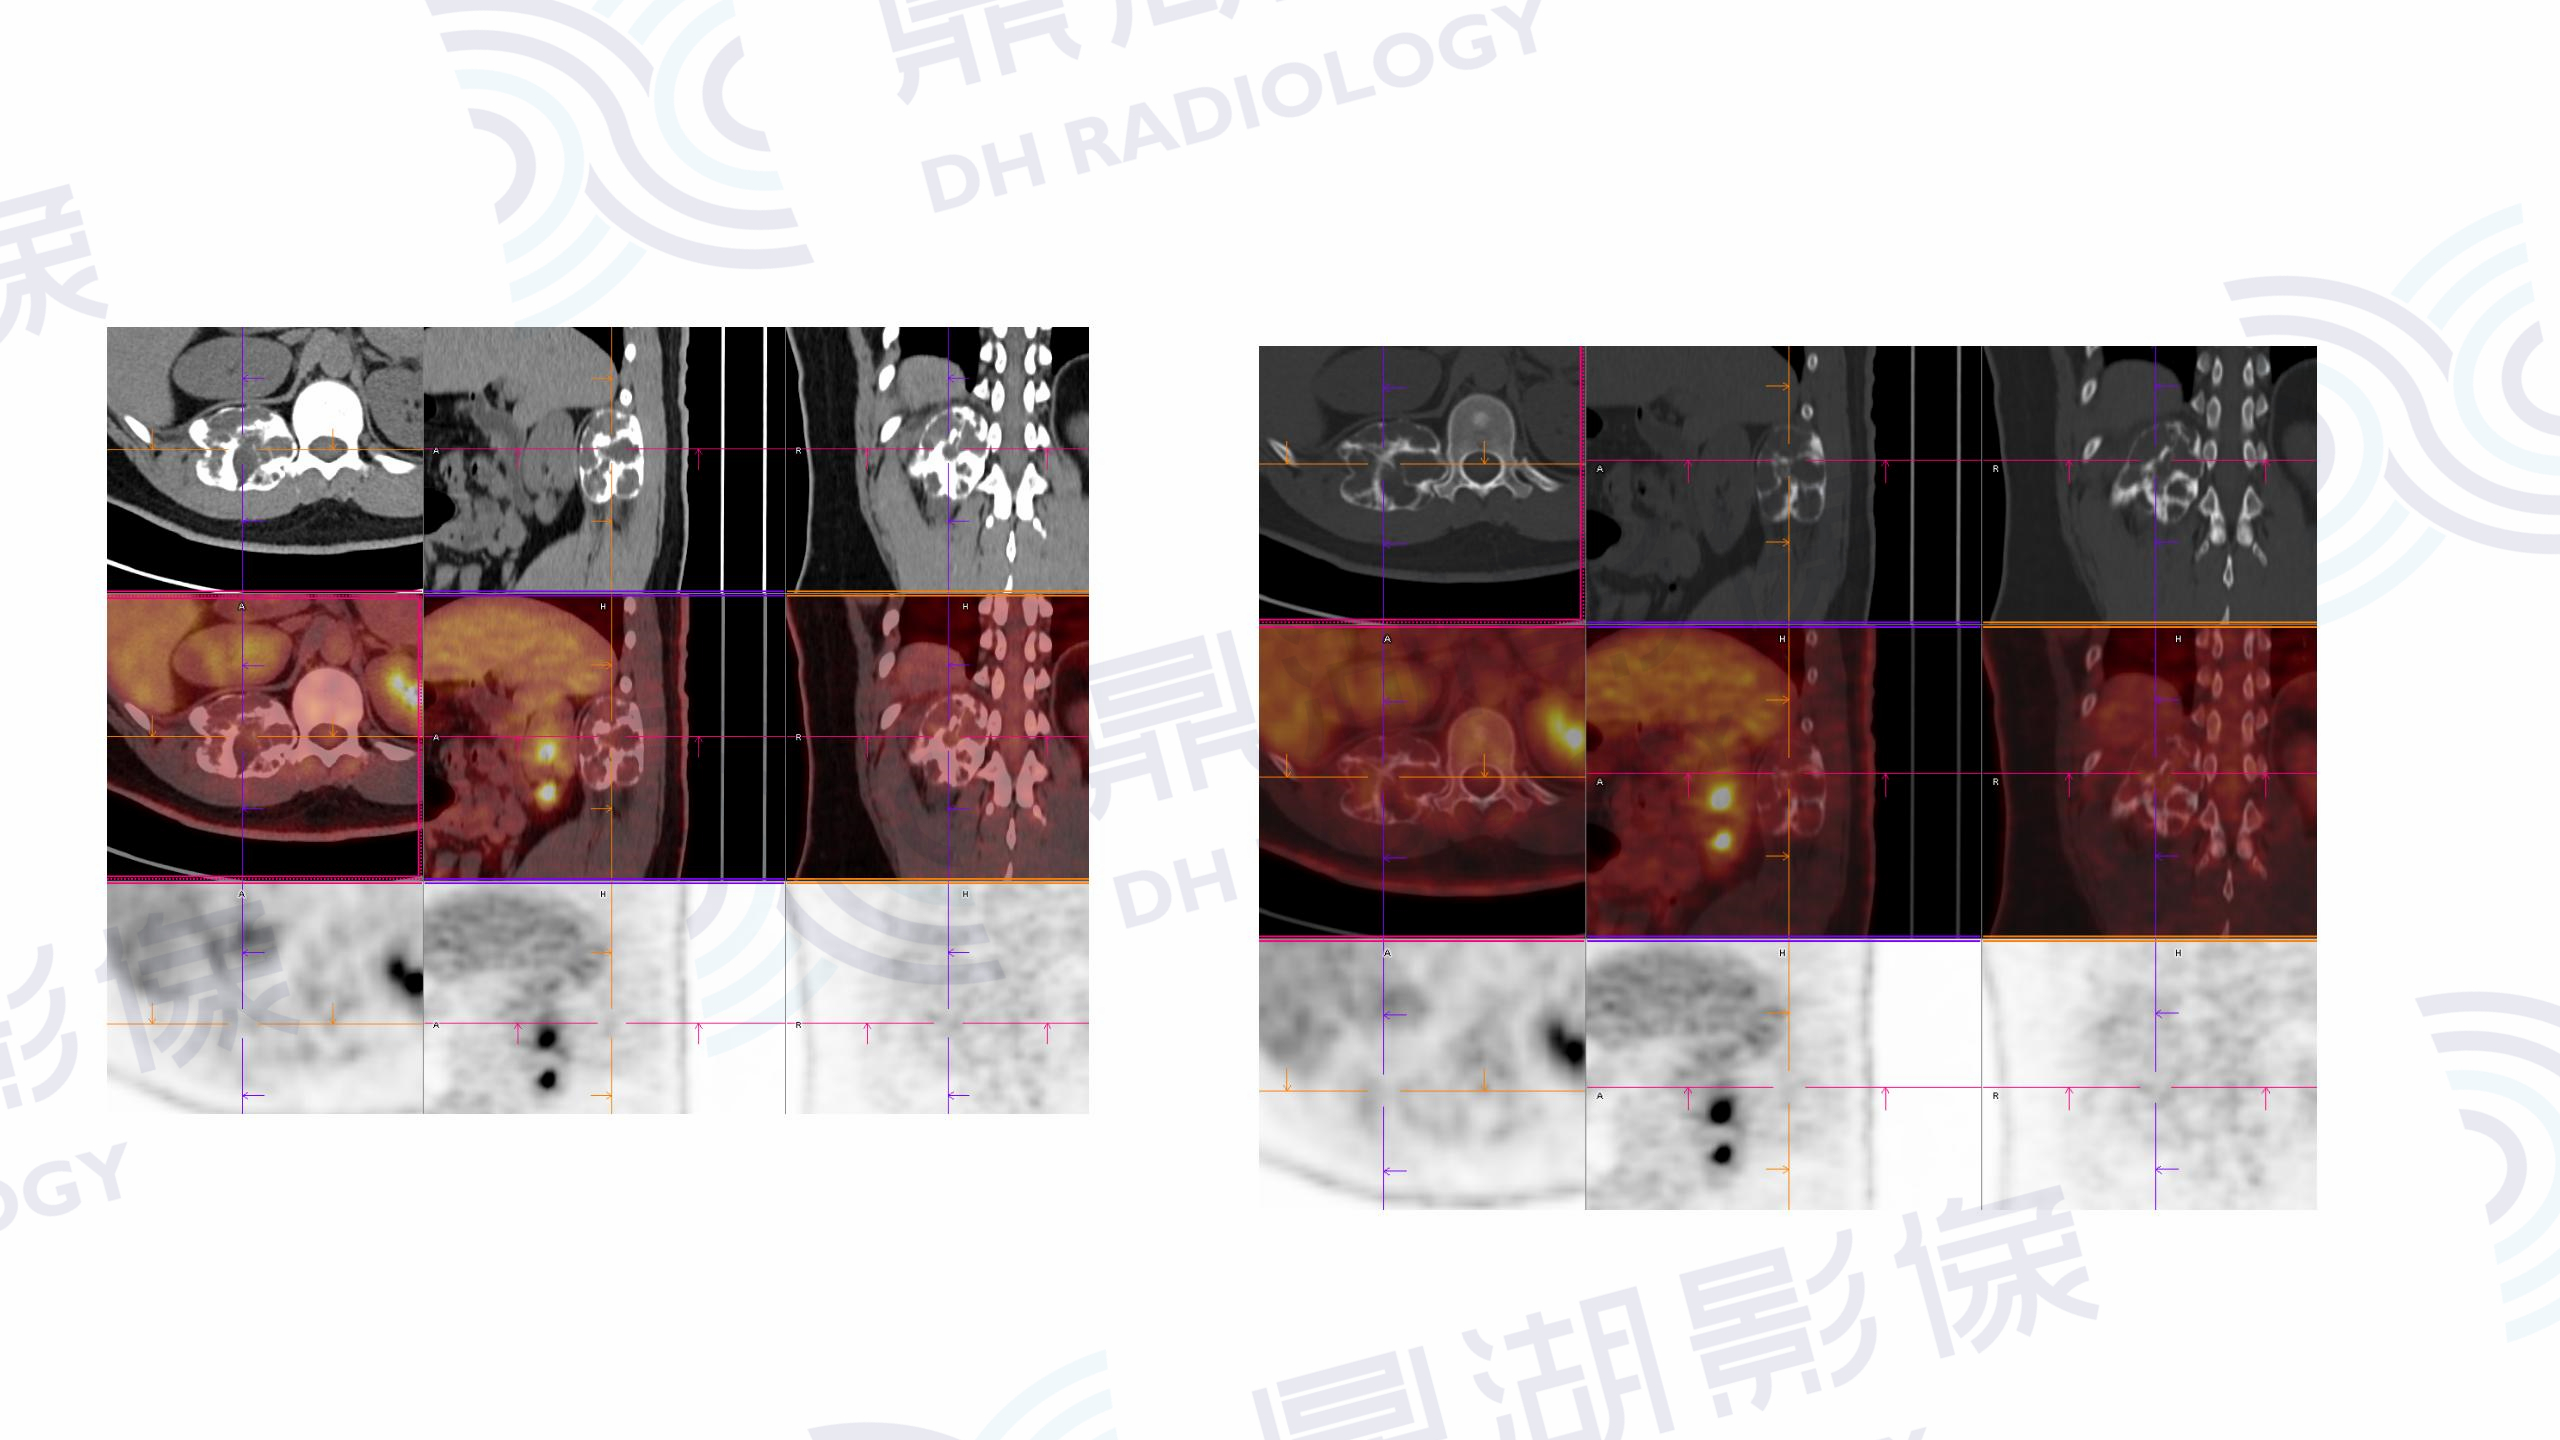

肋骨动脉瘤样骨囊肿

CT

PET

男  18岁

因摔跤到当地医院检查,发现右第12肋骨肿瘤样改变,怀疑肿瘤后进一步行PET/CT检查。